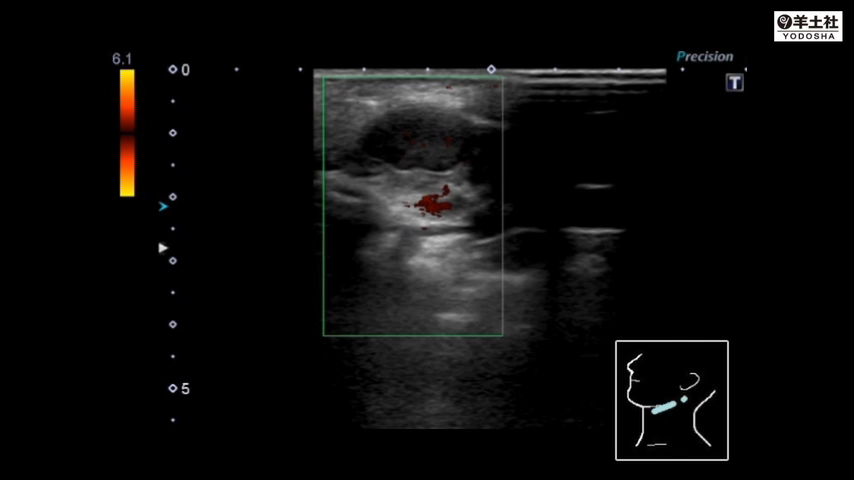

第2章6 ウイルス性リンパ節炎

6 頸部腫脹 〜頸部リンパ節と耳下腺をマスターしよう 難易度★★☆【木下正和】